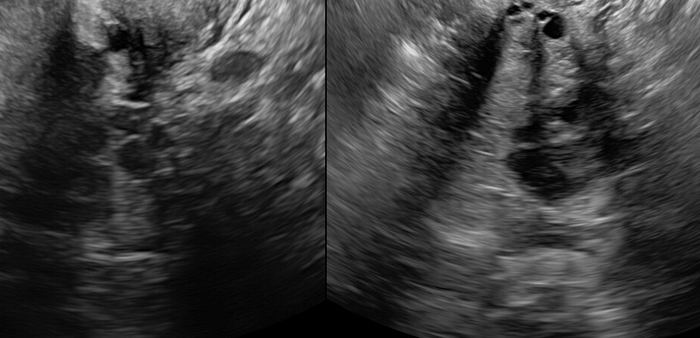

Actual image of my ultrasound

I ended up going to another primary and then she ordered an ultrasound but the ultrasound could not find anything and ended up going to the hospital and they did a CT scan and found my Fibroid so I ended up switching OBGYN and she told me it’s not in your head it’s actually happening and that I have PCOS on top of it all that it was going to cause pain and be difficult.

She ended up doing a pelvic ultrasound and we actually found out that I have adenomyosis which is the opposite of endomitosis. Adenomyosis does not allow the uterus to shed the way it is suppose to meaning you don’t have periods as often and when you do it is heavy and painful. Everything grows inward and nothing sheds causing the uterus to weigh down and enlarge and causes all kinds of issues because it presses on the bowels and other things making it so that you cannot poop and things back up causing nausea, vomiting and diarrhea.